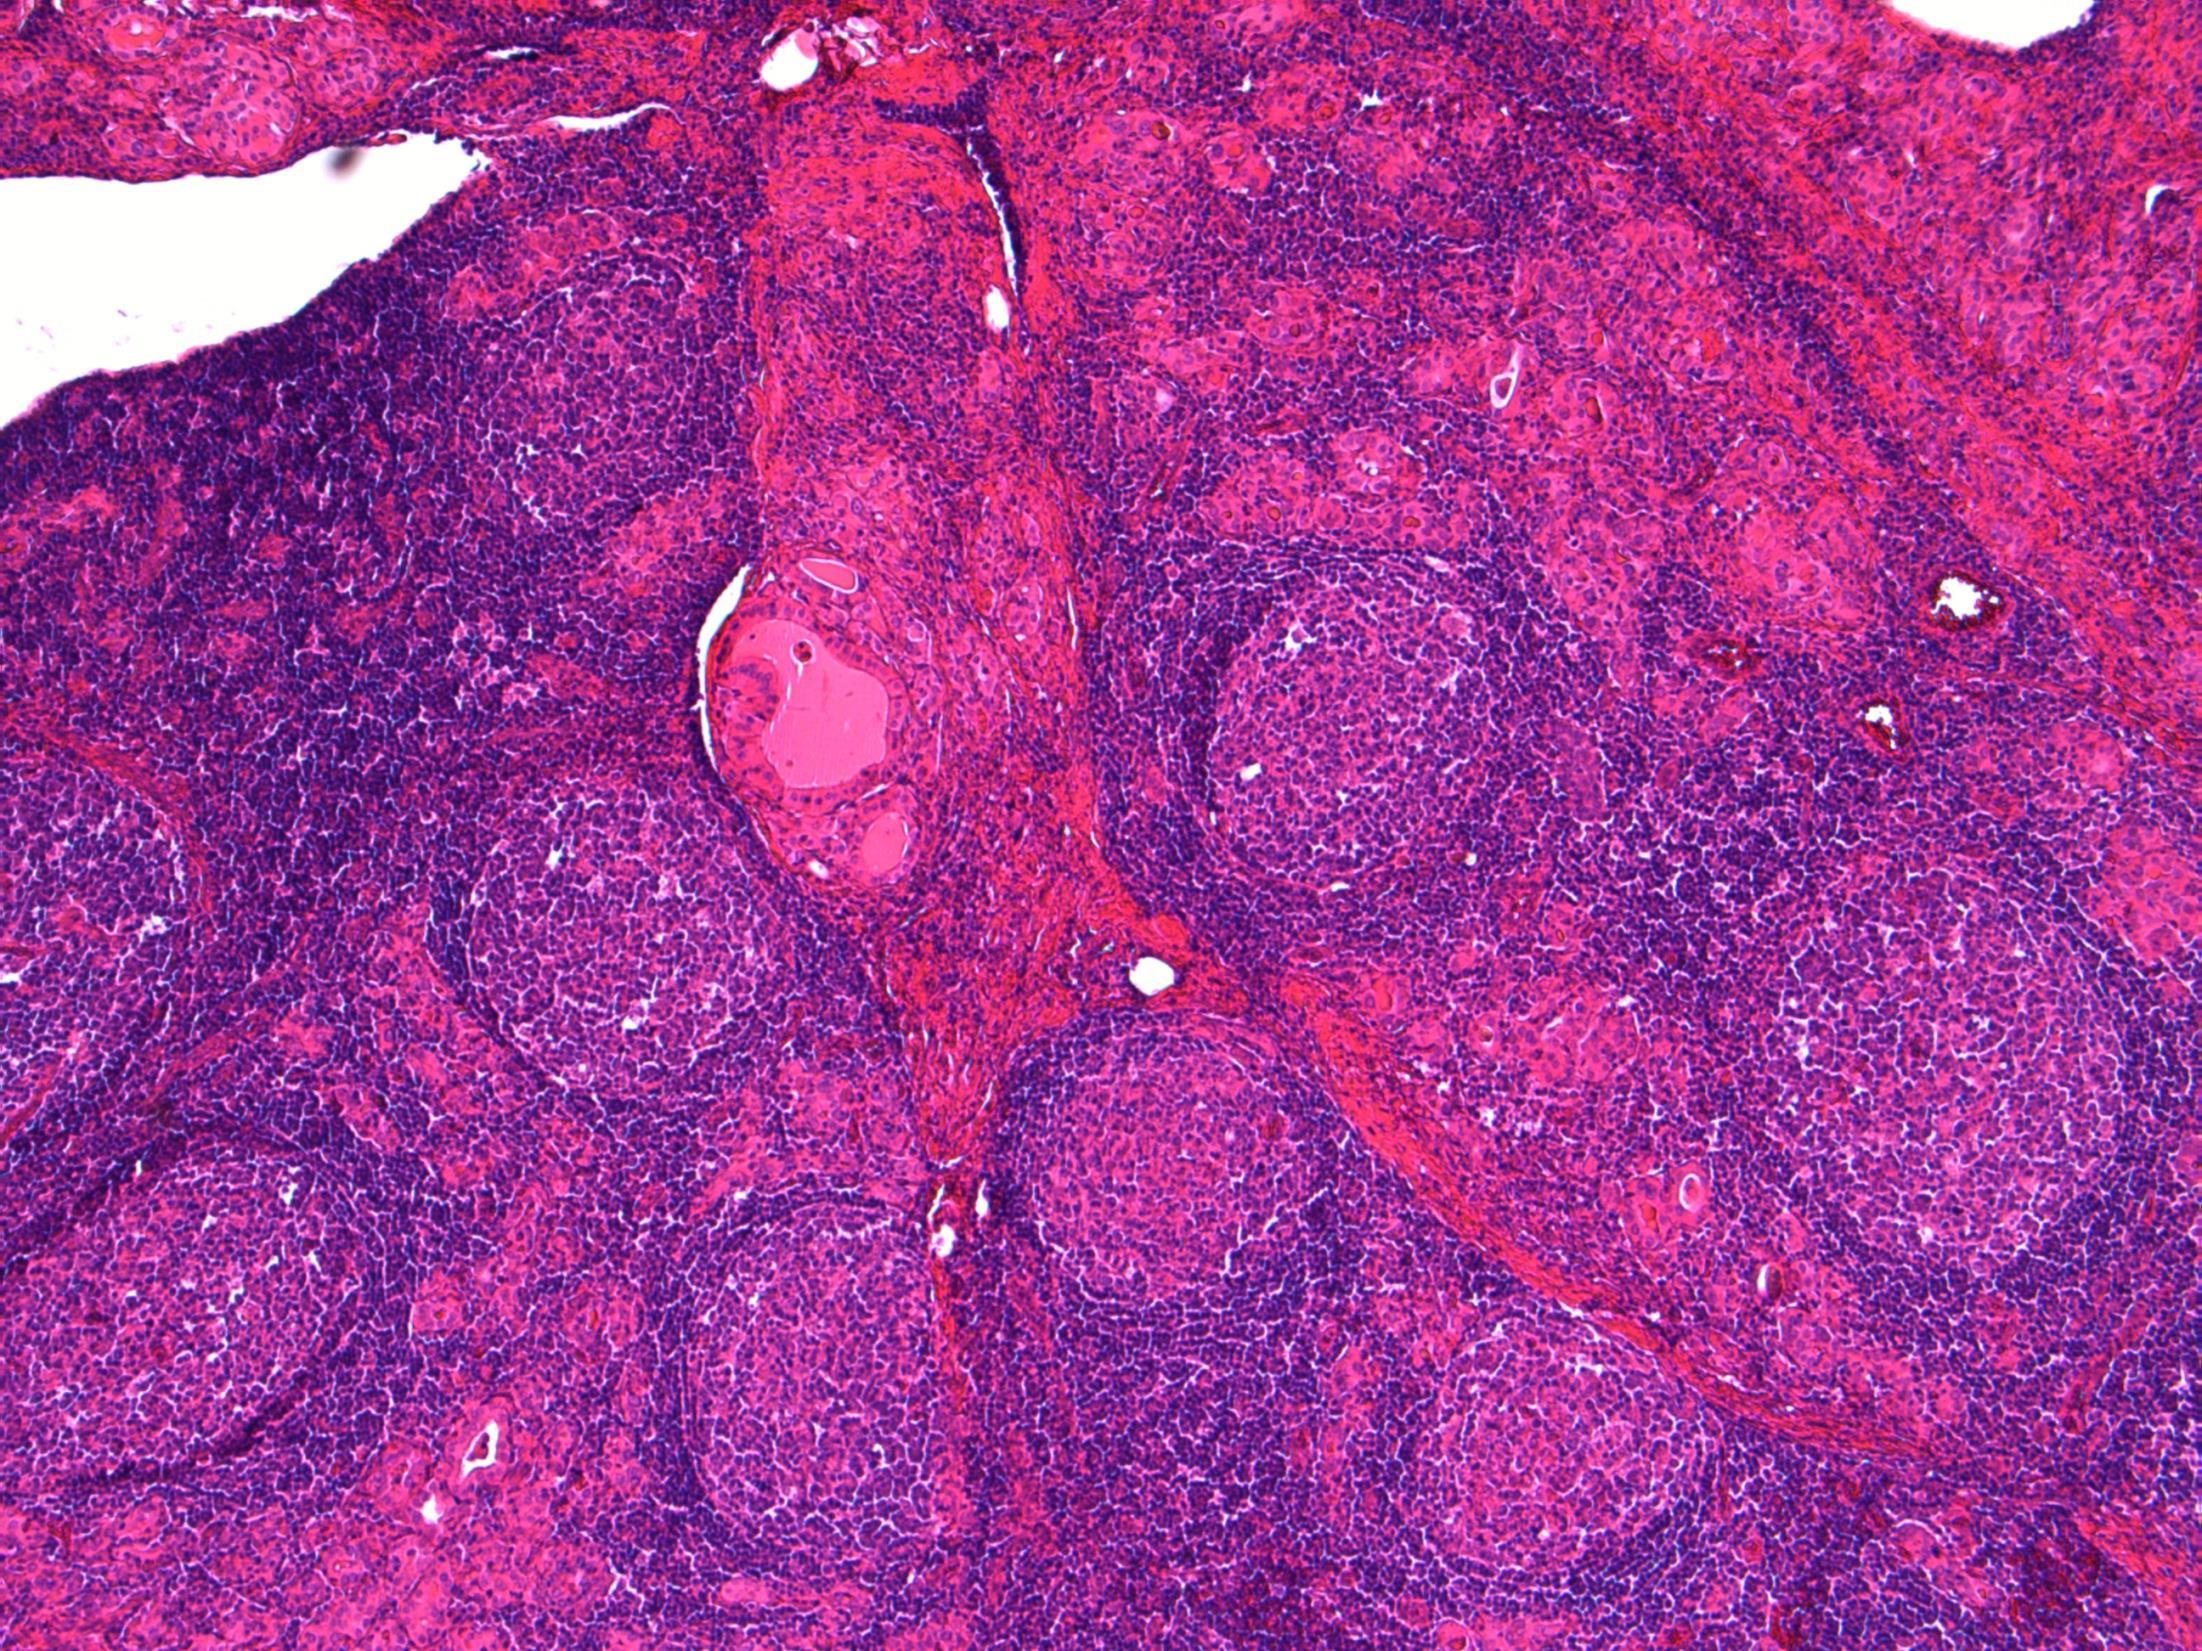

Hashimotos thyroiditis

Description: Extensive lymphocytic infiltrate with germinal centre formation. Plasma cells seen. Atrophic follicles with Hürthle cells. Reduced colloid. Some cleared nuclei but no well-defined nodule.

Diagnosis: Hashimoto’s thyroiditis

Plan:

• Check extra blocks for co-existing PTC or MZL.

• Correlate with history and macro (symmetrical enlargement of both lobes).

• Correlate with autoantibodies, eg TSH.

Comments:

Hashimoto’s thyroiditis

• Almost always in females, usually age 40-50- like in this case.

• Associated with SLE, rheumatoid arthritis, Sjögren syndrome, pernicious anaemia

• Differential Diagnosis:

– Papillary carcinoma – Nuclei in HT often show nuclear clearing, enlargement, overlapping (reactive changes). A well-defined separate nodule should be seen before diagnosing Ca

In a background of HT, areas with a more diffuse, monotonous proliferation of small lymphoid cells with clear cytoplasm; lymphoepithelial lesions and destruction of native follicles

MZL –

3.5 Clinico-pathological correlation 3.0 Differentiation from potential mimics (papillary Ca, MALT lymphoma) 2.5 Description with diagnosis 2.0 Other benign diagnosis 1.5 Favouring or suspicion of a neoplastic process 1.0 Definite malignant diagnosis Case 10